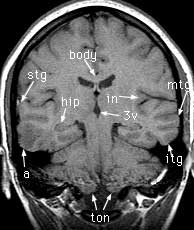

T1 coronals pre-gad

Findings: Focus of low signal in the cortex of the right middle and inferior temporal gyri (a). Cerebral aqueduct (aq) leading from the 3rd (3v) to the 4th (4v) ventricle. Crus of the fornix (crus). Flow enhancement in the sigmoid sinus (sig). Superior (stg), middle (mtg) and inferior (itg) temporal gyri. Hippocampus (hip). Body of the corpus callosum (body). Insula (in). Cerebellar tonsils (ton). Cingulate gyrus (cgy) and sulcus (csu). Body of the caudate nucleus (caud). Horizontal fissure (hor).